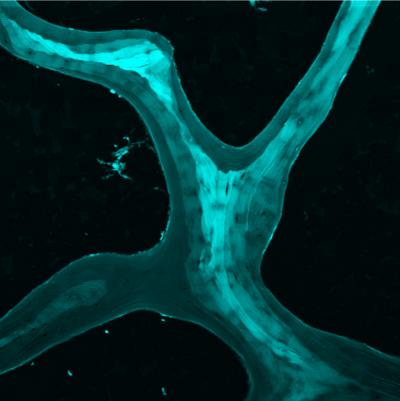

ITHACA, N.Y. - Researchers at Cornell University have discovered that bone does something better than most man-made materials: it bounces back after it breaks. In an article published in the Proceedings of the National Academy of Sciences this week Cornell scientists report that cancellous bone -- the spongy foam-like type of bone found near joints and in the vertebrae that is involved in most osteoporosis-related fractures -- displays unique material properties that allow it to recover shape after it breaks.

"Cancellous bone does the opposite, it has softer surfaces with a more brittle interior," says Christopher Hernandez, Associate Professor of Mechanical and Aerospace Engineering and Biomedical Engineering and principal investigator on the project. The combination of softer surfaces and brittle interior allows cancellous bone to direct cracks to locations where they are less detrimental, allowing the structure to recover its shape -- bounce back -- after it breaks.

The discovery provides a compelling answer to the long-standing question as to why bones have foam-like regions. "We used to think that we had cancellous bone for the same reasons that we use foams in engineering, to absorb energy or make the structure more lightweight, but it turns out that cancellous bone does something different, the way cancellous bone breaks actually makes it heal better," says Hernandez.